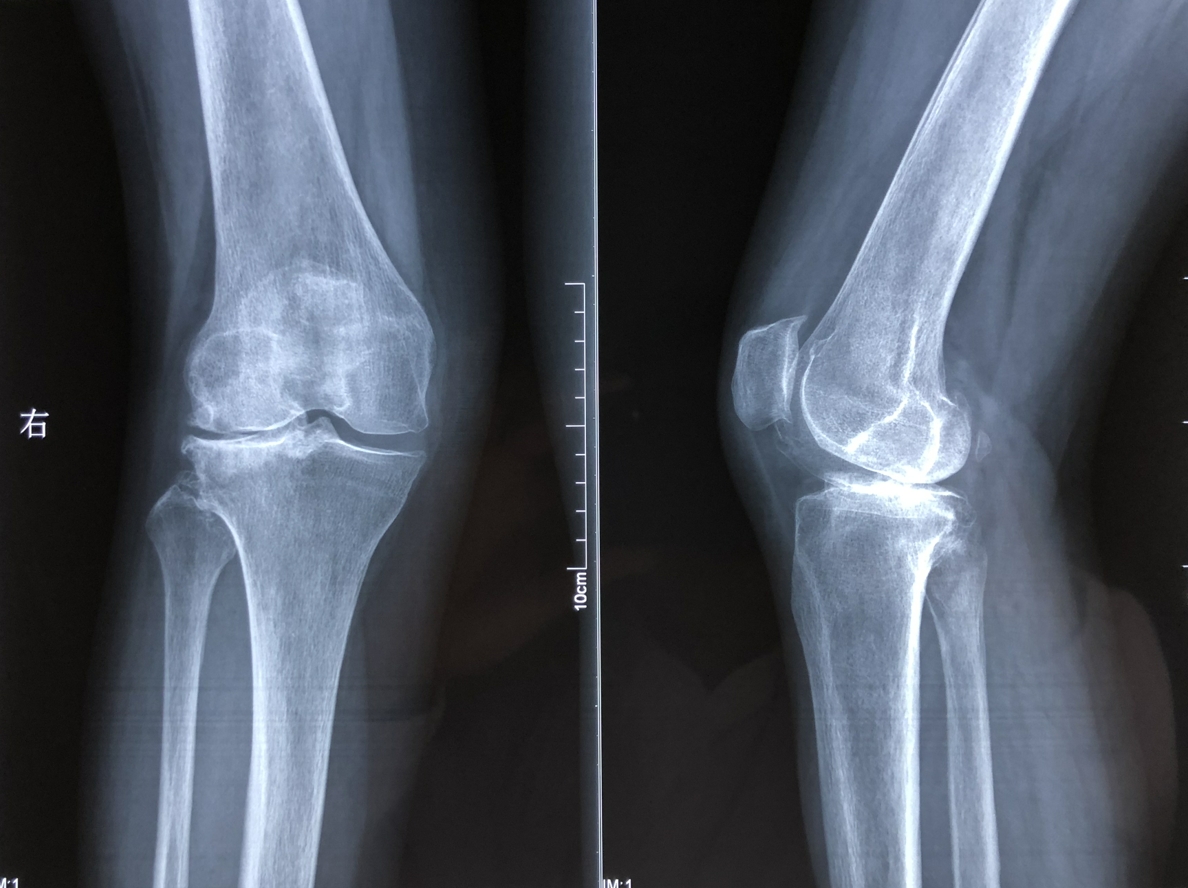

1、关节炎

手脚关节肿胀可能是关节炎的症状,如类风湿性关节炎或者骨关节炎。关节炎的治疗通常包括药物、物理治疗和改变生活方式。